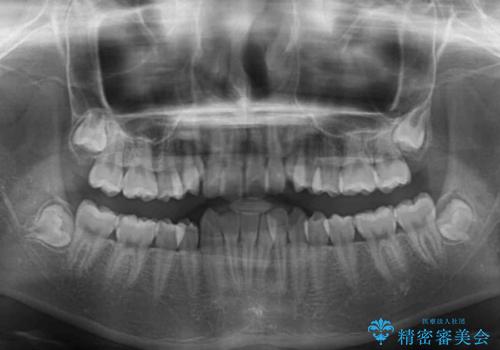

- 上下前歯のデコボコを気にして来院された患者様です。

前歯の叢生は強かったのですが、口元が引っ込んでいる印象であったため、非抜歯にて矯正治療を行うこととしました。